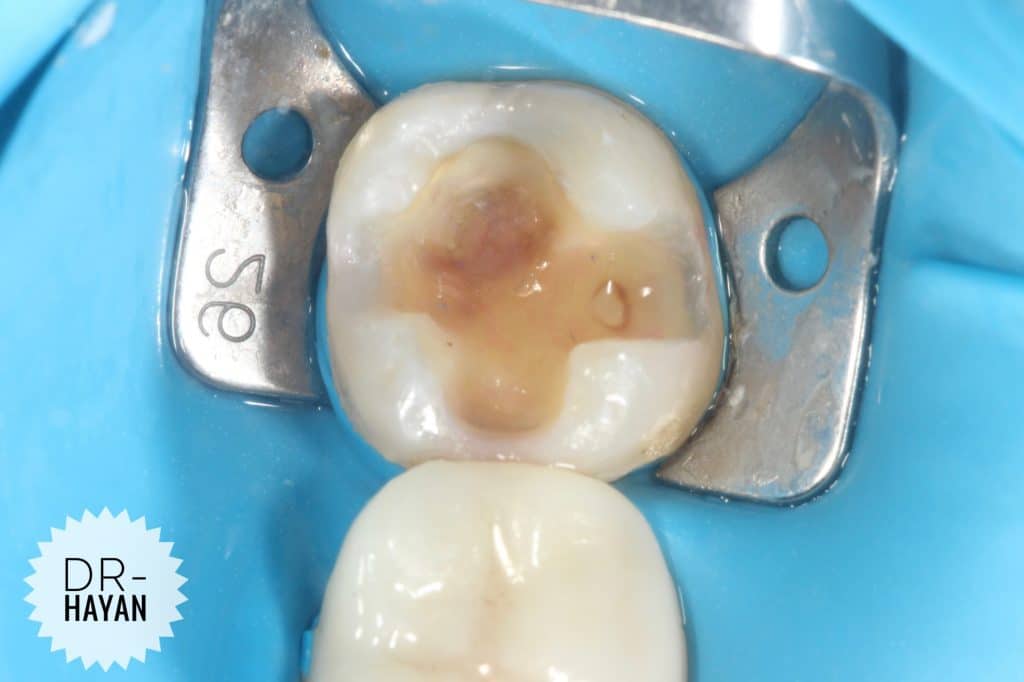

First Bulding up of buccal & lingual wall

Laying technique

Start with large cusp

1ry & 2ry Anatomy

Finishing it

Finally